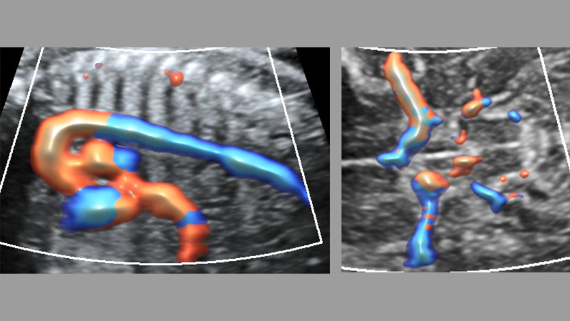

ImГЎgenes ClГӯnicas